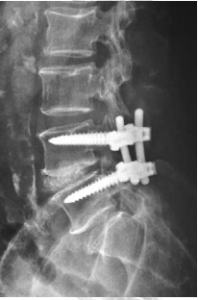

Findings at surgery were severe central and subarticular stenosis at L45 with hyperrophic facet and dural cyst. Decompression laminectomy followed by pedicle screws instrumentation and interbody fusion was carried out.

Mr A did very well and dorsiflexion of the foot improved quickly to grade 4+/5 the next day. He graduated from walking with support to independent walking. He was also found to have an unrelated compression fracture of T6 (old) and T8 (recent) which were treated conservatively.